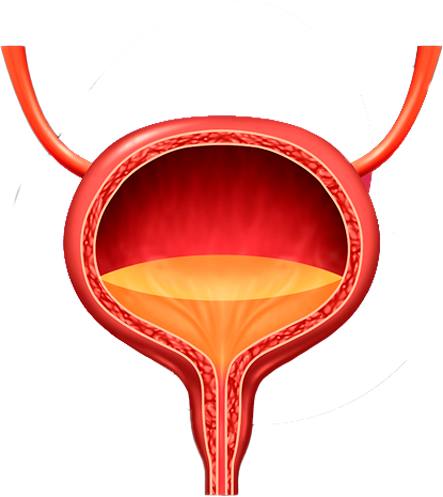

Tengo como compromiso mejorar la salud de nuestra comunidad y promover la prevención de patologías que afectan al aparato urinario, glándulas suprarrenales y retroperitoneo de ambos sexos, y el aparato reproductor masculino.

El Dr. Alejandro Palmeros Rodríguez es un médico especialista en urología comprometido con el bienestar de sus pacientes. Mediante su conocimiento y el uso de tecnología puede lograr la recuperación de distintos padecimientos y lograr una vida sana.

“Gracias a la prevención, el doctor pudo identificar una infección en etapa temprana”

- Lourdes Campos Uribe